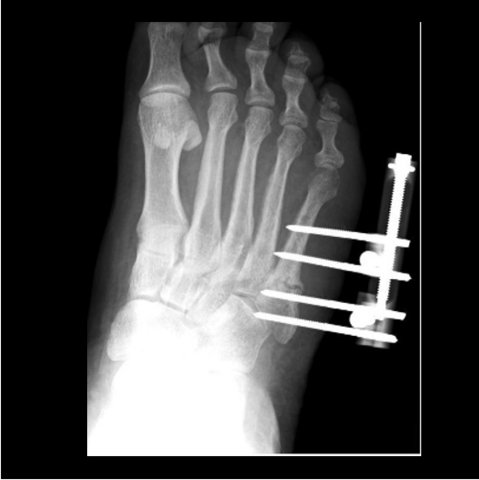

Figure 5a

Figure 5a. The 24-year-old required hardware removal and application of external fixation for gradual compression. Most cases heal within 6 weeks with gradual compression weekly.

Figure 5b

Figure 5b. The 24-year-old required hardware removal and application of external fixation for gradual compression. Most cases heal within 6 weeks with gradual compression weekly.

-

Figure 5c

Figure 5c. The 24-year-old required hardware removal and application of external fixation for gradual compression. Most cases heal within 6 weeks with gradual compression weekly.

Figure 5d

Figure 5d. The 24-year-old required hardware removal and application of external fixation for gradual compression. Most cases heal within 6 weeks with gradual compression weekly.